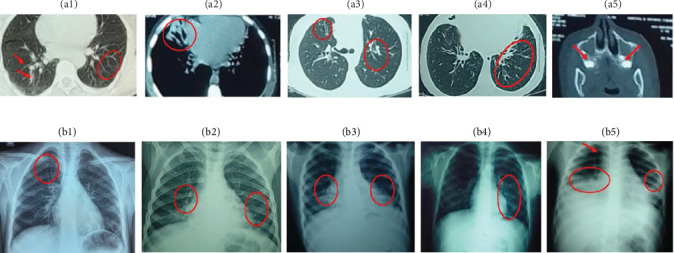

主要组织相容性复合体类(MHC)-II缺乏症是一种罕见的常染色体隐性联合免疫缺陷,占北非和中东先天性免疫缺陷(IEI)病例的4.1%。大多数患者活不过10岁。本研究中描述的MHC-II缺乏症罕见且不寻常。我们报告了四例摩洛哥血统的MHC-II缺乏症无关患者。采用流式细胞术对淋巴细胞亚群进行免疫分型和人白细胞抗原dr (HLA-DR)表达分析。通过直接测序进行遗传分析。患者的平均年龄为18.75岁(16-26岁);平均诊断年龄14.07岁,平均发病年龄5.25个月。临床表现为复发性肺部感染,以支气管扩张和出血性直肠结肠炎为主。所有患者均无HLA-DR表达,并在RFXANK中检测到c.338-25_338del突变。我们的3名患者(75%)仍然活着,并每月接受静脉注射免疫球蛋白(IVIG)治疗。在所有年龄组的联合免疫缺陷的鉴别诊断中考虑MHC-II缺乏是很重要的。需要进一步的研究来阐明与这种情况相关的各种表型。

Major histocompatibility complex class (MHC)-II deficiency is a rare autosomal recessive combined immunodeficiency, accounting for 4.1% of inborn errors of immunity (IEI) cases in North Africa and the Middle East. Most patients do not survive beyond the age of 10 years. The cases described in this study are rare and unusual for MHC-II deficiency. We report the cases of four unrelated patients of Moroccan origin with MHC-II deficiency. Immunophenotyping of lymphocyte subpopulations and analysis of human leukocyte antigen-DR (HLA-DR) expression were performed using flow cytometry. Genetic analysis was conducted through direct sequencing. The mean age of our patients was 18.75 years (range 16-26 years); the mean age at diagnosis was 14.07 years, and the mean age of onset of symptoms was 5.25 months. The clinical presentation is characterized by recurrent pulmonary infections with predominant bronchial dilatation and hemorrhagic rectocolitis. The diagnosis was confirmed in all patients by absence of HLA-DR expression and detection of the c.338-25_338del mutation in RFXANK. Three (75%) of our patients are still alive and are on monthly intravenous immunoglobulin (IVIG) therapy. It is important to consider MHC-II deficiency in the differential diagnosis of combined immunodeficiencies across all age groups. Further studies are needed to elucidate the various phenotypes associated with this condition.